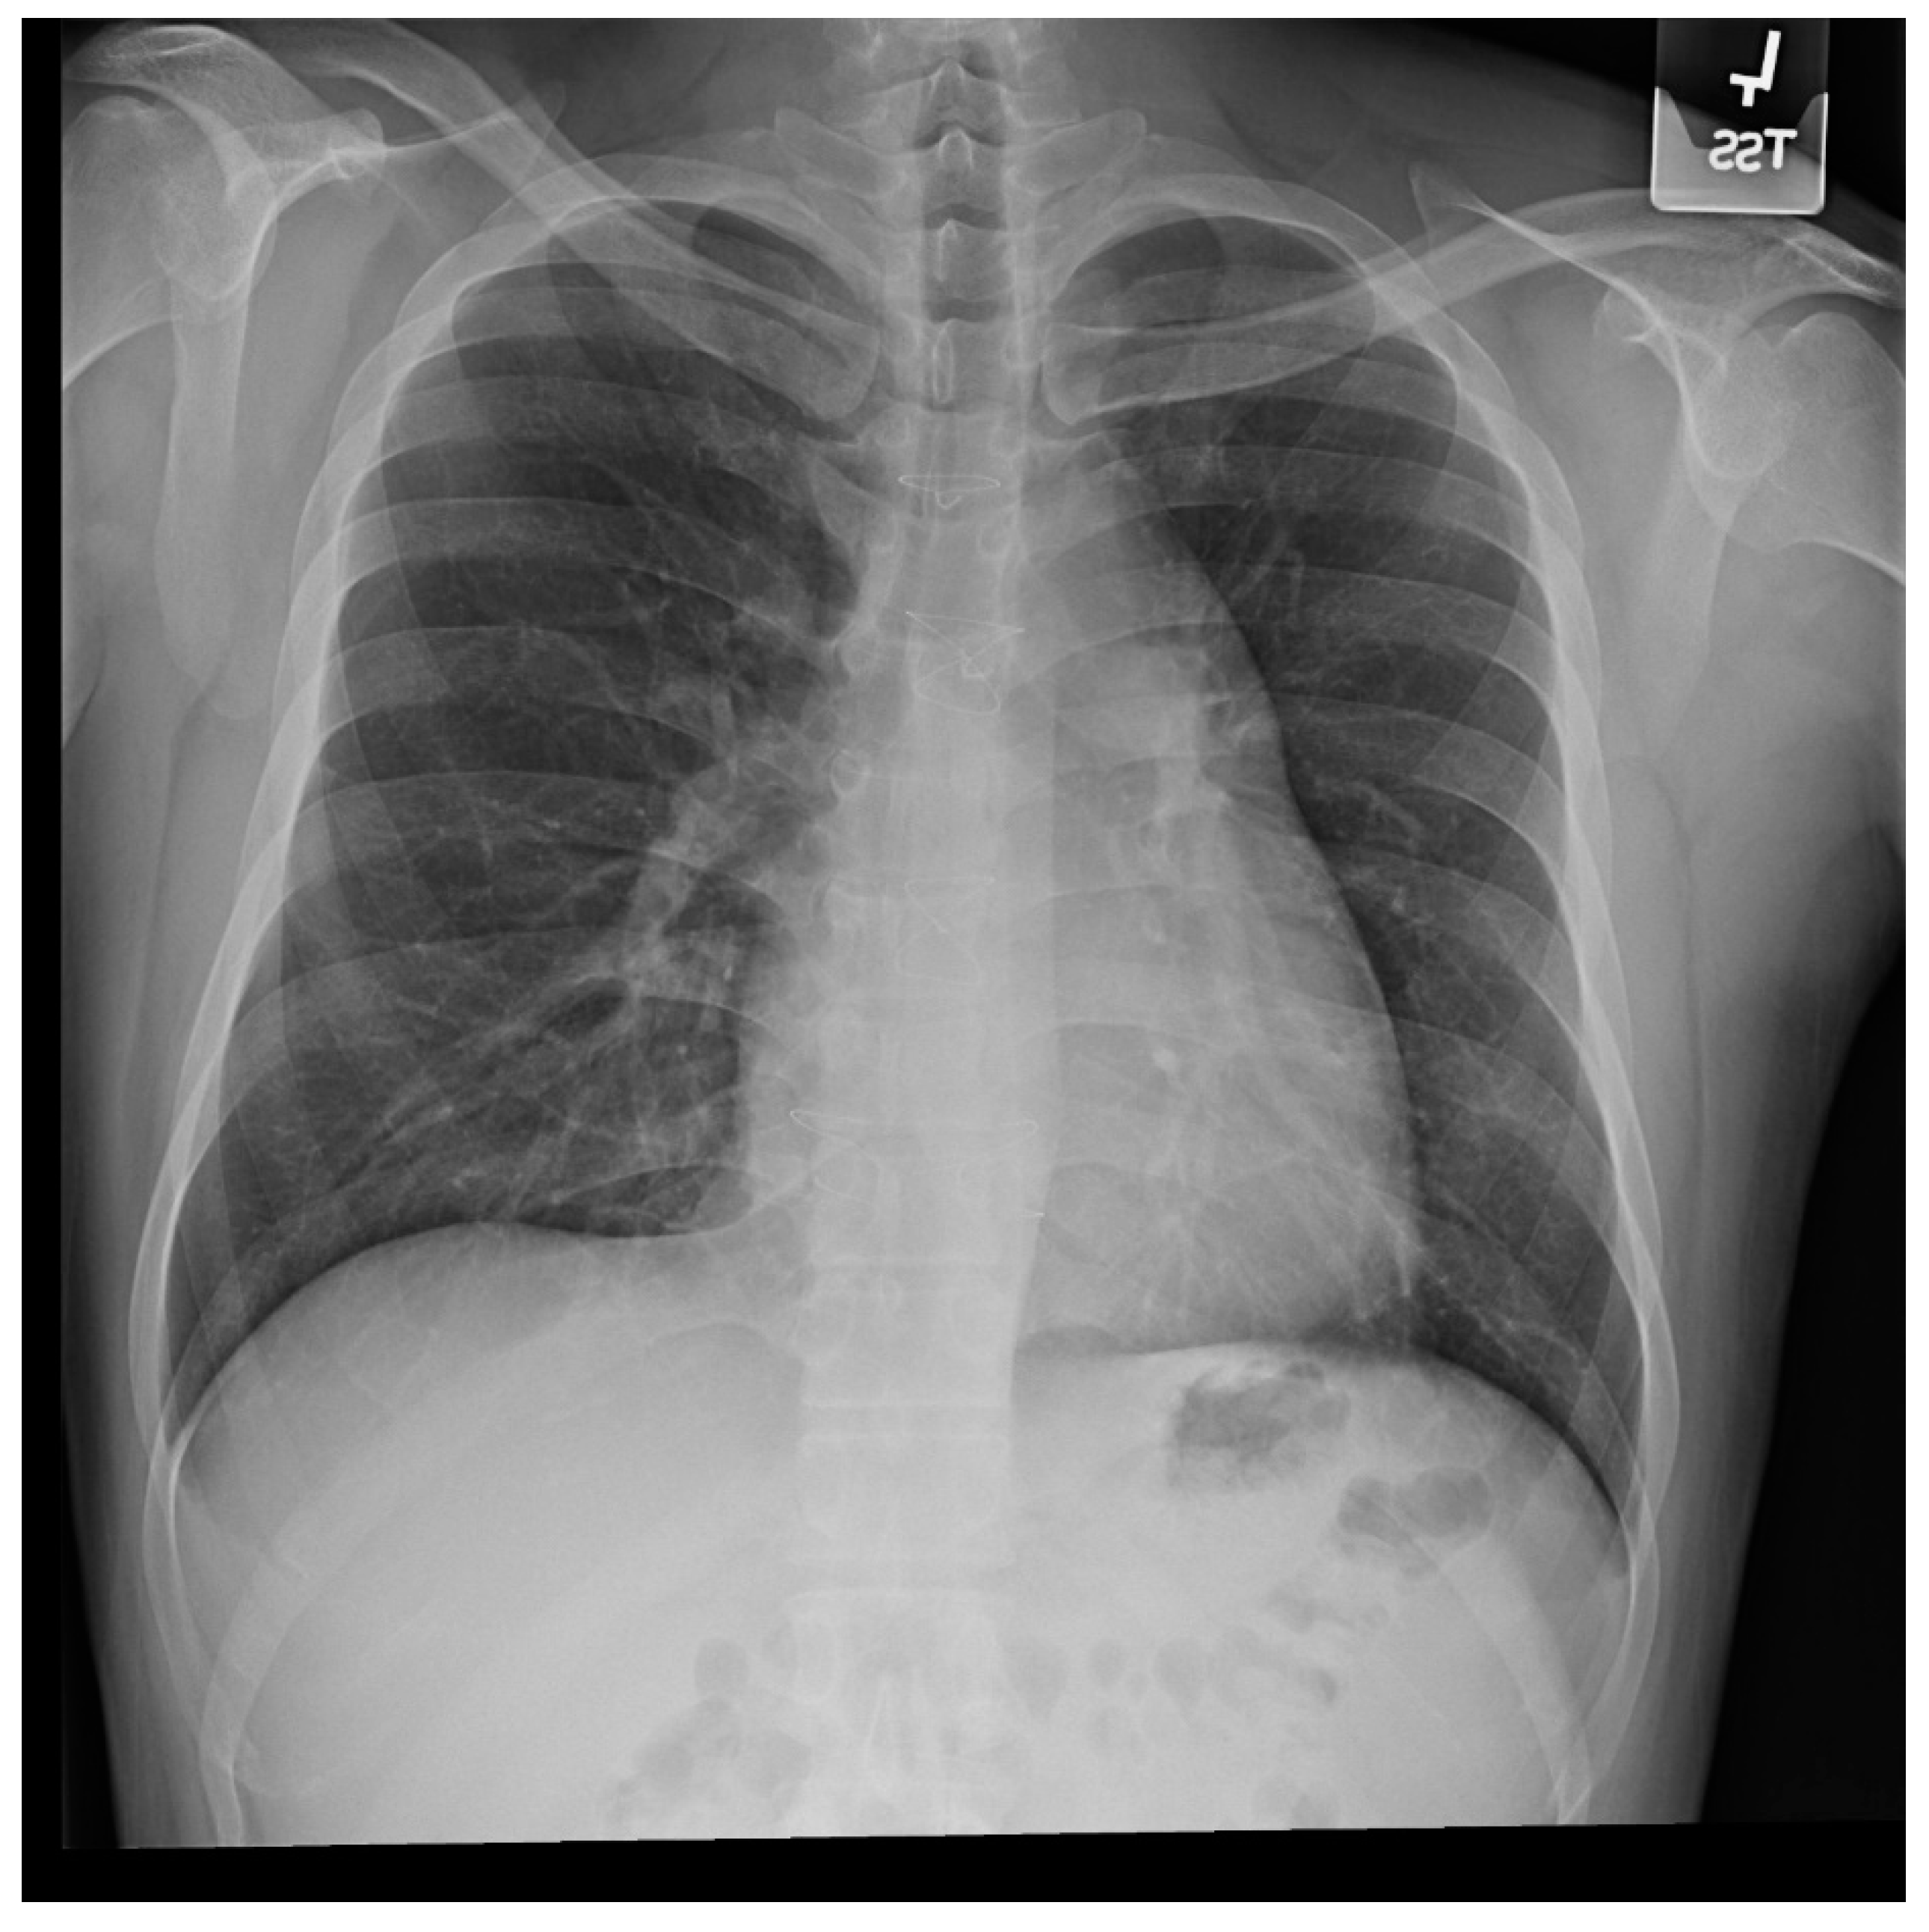

Figure 23.

Posteroanterior chest X-ray in an adult with previously operated tetralogy of Fallot: the chest X-ray was obtained in a 21-year-old female with exertional dyspnea. She was cyanotic at birth and diagnosed with tetralogy of Fallot. She had a Blalock-Thomas-Taussig (BTT) shunt (palliative subclavian artery to pulmonary artery shunt) at 10-months-of-age. At 3-years-old she underwent complete repair with closure of the ventricular septal defect, right ventricular (RV) outflow tract reconstruction with pericardium, with transannular patch and ligation of the BTT shunt. This posteroanterior chest X-ray is well centered and the inspiration is good. The cardiothoracic ratio is increased and the cardiac silhouette is boot-shaped (“coeur en sabot”). The right heart border is prominent, suggesting right atrial enlargement. The pulmonary vascularity is normal and the lung fields and pleura are clear.